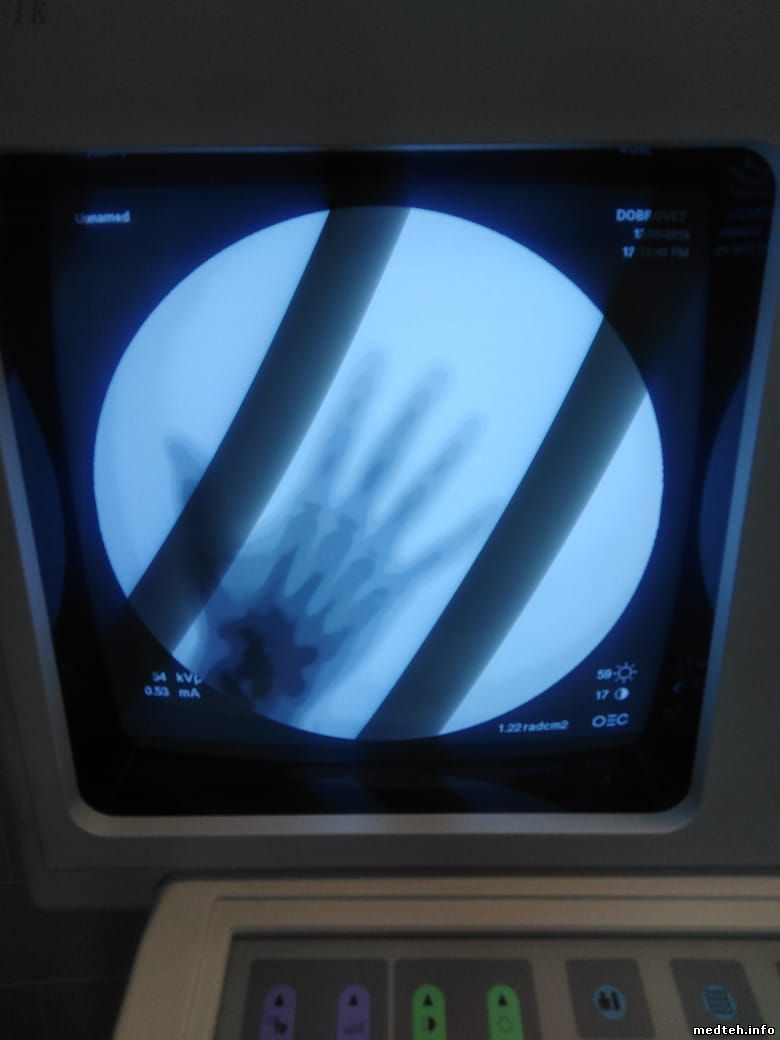

Собственно фото Зум крутил - эффекта нет.

3641326.jpg (45.0 Kb)